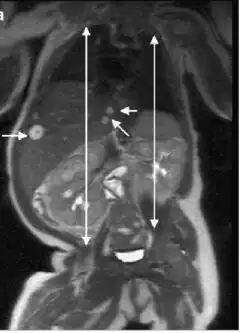

| Adrenal gland: Beckwith-Wiedemann syndrome Nuclear enlargement and hyperchromasia with nuclear "pseudoinclusion" near the center of field. Mitotic figures were not identified. | |

- Visceromegaly involving one or more intra-abdominal organs including liver, spleen, kidneys, adrenal glands, and/or pancreas

- Cytomegaly of the fetal adrenal cortex (pathognomonic)